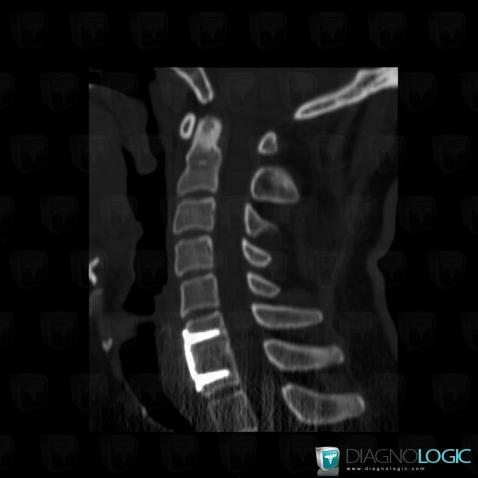

Postoperative, Vertebral body / Disk, CT

Here is the specific information in the key image above:

- Diagnosis Postoperative, Location(s) Vertebral body / Disk, with gamuts Block vertebrae